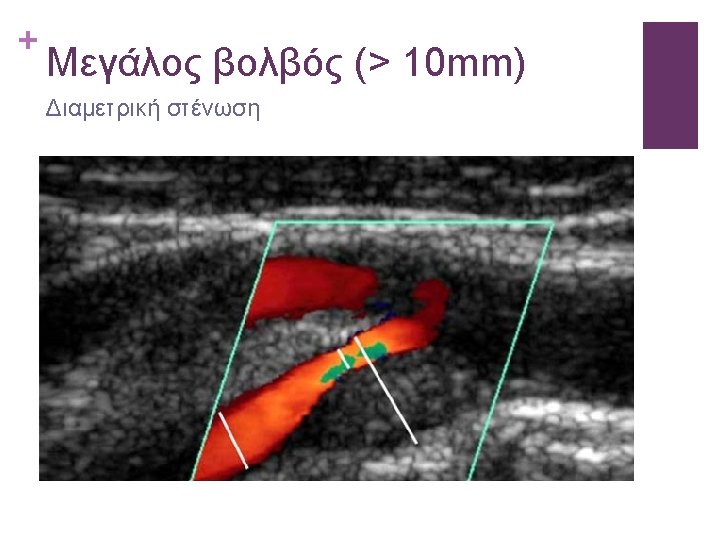

ICA STENOSIS CRITERIA Washington University / Eugene Strandness criteria GRADE CRITERIA A (normal) PSV <120 cm/s. No SB B (1 -15%) PSV<120. SB during acceleration of systole. Window above EDF C (16 -49%) PSV <120. SB throughout systole. No window above EDF D (50 -79%) PSV>120. SB throughout systole. No window D+ (80 -99) PSV>120. SB throughout systole. No window. EDF<135 cm/s E (occlusion) No flow signal PSV: Peak Systolic Velocity, EDF: End Diastolic Frequency, SB: spectral broadening

PSVICA, EDVICA, PSV ratio (ICA/CCA)